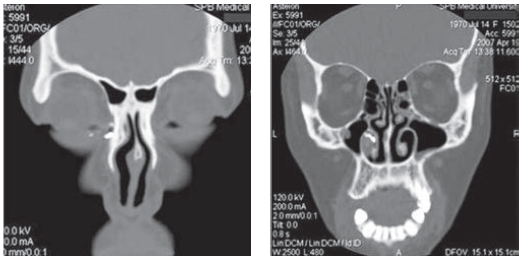

КТ слезоотводящих путей (компьютерная томография слезоотводящих/носослезных путей) с контрастом позволяет установить факт непроходимости слезных путей и выявить уровень закупорки или сужения (стеноза). Кроме этого, на КТ будет видна перегородка носа, носовые раковины и все околоносовые пазухи, что позволит докторам выявить весь комплекс, влияющий на слезотечение и нагноение, и спланировать полноценное лечение, которое гарантированно приведет к улучшению.

КТ слезоотводящих путей с контрастом позволяет определить размеры слезных протоков, слезного мешка и носослезного канала, оценить их проходимость и просвет, проанализировать окружающие костные и мягкотканные структуры, толщину костей, спланировать лечение, в том числе - хирургическое.